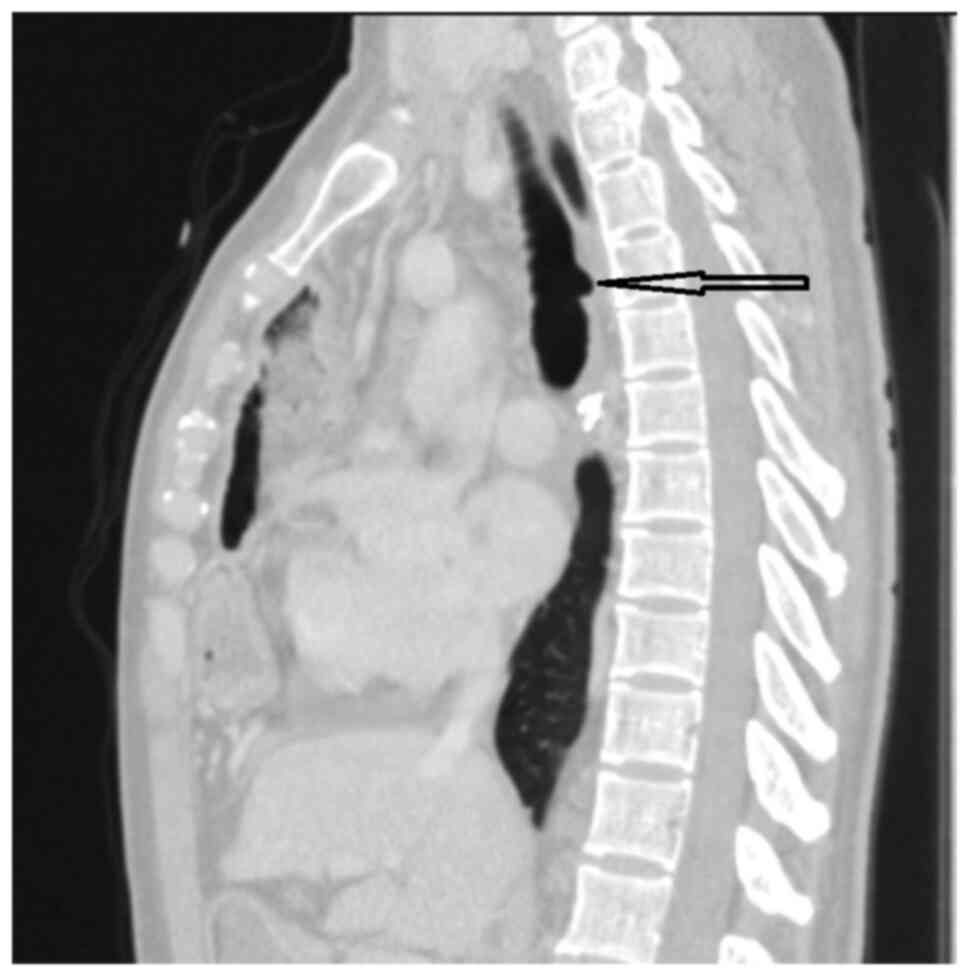

Acquired benign tracheo‑oesophageal fistula secondary to oesophageal stenting for post lye ingestion stenosis: A case report

Acquired benign trachea‑oesophageal fistula is a rare benign pathological entity with varying aetiologies that most often occurs post‑intubation. This case report presents the case of a female patient, 31 years old, admitted to the emergency room with sepsis syndrome following bilateral aspiration pneumonia caused by a large trachea‑oesophageal fistula. The fistula was the result of intra‑tracheal migration of an oesophageal stent placed for post lye ingestion stenosis. Esophageal diversion and partial resection with oesophageal patch to repair the tracheal defect, under general anaesthesia with ventilation using rigid bronchoscopy and high frequency jet ventilation (HFJV), followed at a later date by esophageal replacement with colic graft were the procedures performed with a view to curing the patient. In conclusion, complex cases always require a tailored approach. It is important to note that HFJV may be applied for a longer period of time and the oesophagus can be used as patch for the posterior tracheal wall in selected cases. Staged surgery is also an option when the patients' poor health status does not permit major surgery.